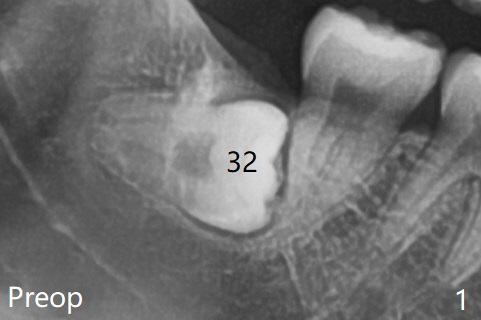

A 27-year-old woman (nervous) is going to return for #16 and 17 extraction (Fig.1).